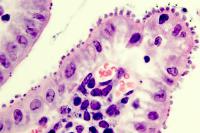

Intestinal tissue infected with Cryptosporidium, with arrows pointing to the parasites in the upper right corner of the frame.

Image courtesy of Sumiti Vinayak